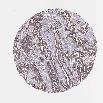

OVARIAN CANCER - Protein expressioni

A mouse-over function shows sample information and annotation data. Click on an image to view it in a full screen mode. Samples can be filtered based on level of antibody staining by selecting one or several of the following categories: high, medium, low and not detected. The assay and annotation is described here.

Note that samples used for immunohistochemistry by the Human Protein Atlas do not correspond to samples in the TCGA dataset.

Antibody stainingi

Antibody staining in the annotated cell types in the current human tissue is reported as not detected, low, medium, or high, based on conventional immunohistochemistry profiling in selected tissues. This score is based on the combination of the staining intensity and fraction of stained cells.

Each image is clickable and will lead to virtual microscopy that enables deeper exploration of all samples and also displays staining intensity scores, fraction scores and subcellular localization as well as patient and tissue information for each sample.

Antibody HPA029159

Antibody HPA029160

Antibody CAB000108

Antibody CAB001950

Staining

High

Medium

Low

Not detected

Cystadenocarcinoma, serous, NOS

Carcinoma, endometroid

Cystadenocarcinoma, mucinous, NOS

Carcinoma, NOS